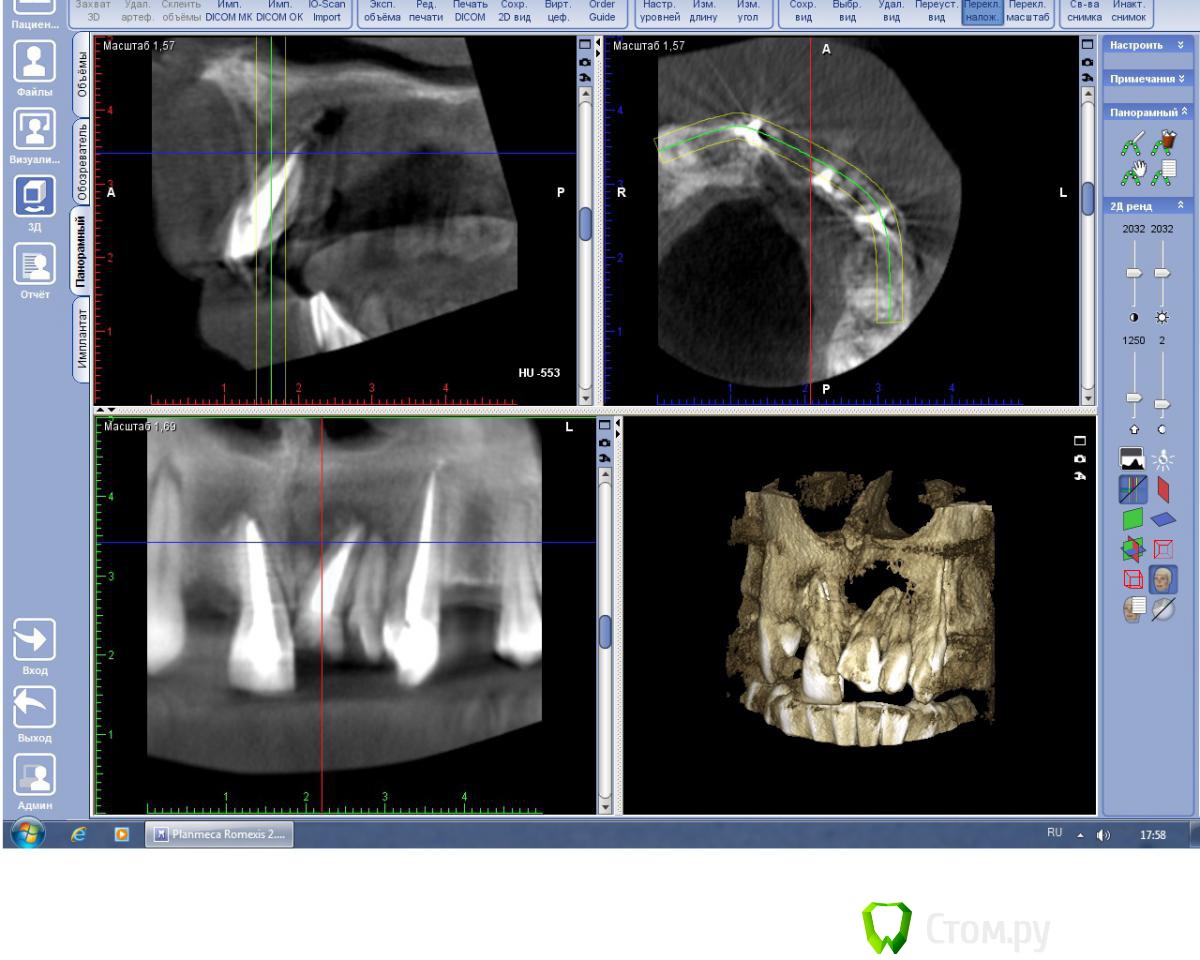

BryanDoc Опубликовано 5 февраля, 2014 Поделиться Опубликовано 5 февраля, 2014 (изменено) Пациент 25 лет обратился в клинику с нагноившейся кистой верхней челюсти слева, абсцесс передней трети твердого неба.На первом этапе проведено вскрытие абсцесса, после стихания острых явлений, установлена декомпрессионная трубка от системы с вестибулярной поверхности, и проверена витальность фронтальных зубов(Эндофрост), витальным оказался только 22 зуб, 21 и 11 зуб --апекс IRM, потом инжектор, 23-- инжектор, удалены корни 12, 24, 36 зубов проведена пародонтология, на последней КТ результат через 8 месяцев консервативного лечения.На начальном этапе подвижность 21, 11 была 3 степени, сейчас подвижности нет.У меня возник вопрос по поводу происхождения кисты? Подозрение что это носо-небная киста, по нескольким критериям---1--отклонение корня 21 зуба, располагается между 11 и 21 , и при эндодонтии 21 и 11 зубов было слизистое отделяемое в канале зубов из кисты.Доктора кто что думает на этот счет?так как дальнейшая тактика если это все таки носо-небная киста то это цистэктомия, через некоторое время. Изменено 5 февраля, 2014 пользователем BryanDoc Ссылка на комментарий

kriokov Опубликовано 5 февраля, 2014 Поделиться Опубликовано 5 февраля, 2014 У меня возник вопрос по поводу происхождения кисты? думаю, что радикулярная (воспалительная) от 21.1. очаг деструктивный в обл 21 , корень выстоит в костный дефект2. консервативное лечение 21 дало + динамику3. киста носо-небная не воспалительного генеза4. носонебный идет в обл между небными отрастками верхней челюсти и межчелюстной, т.е чаще по центру располагается4. можно было бы на кт до лечения посмотреть весь канал на аксиальных срезахДумаю нормально все будет после лечения, кт в динамике , и на живучесть 22 и 13 в динамике. 2 Ссылка на комментарий

BryanDoc Опубликовано 6 февраля, 2014 Автор Поделиться Опубликовано 6 февраля, 2014 (изменено) думаю, что радикулярная (воспалительная) от 21.1. очаг деструктивный в обл 21 , корень выстоит в костный дефект2. консервативное лечение 21 дало + динамику3. киста носо-небная не воспалительного генеза4. носонебный идет в обл между небными отрастками верхней челюсти и межчелюстной, т.е чаще по центру располагается4. можно было бы на кт до лечения посмотреть весь канал на аксиальных срезахДумаю нормально все будет после лечения, кт в динамике , и на живучесть 22 и 13 в динамике. Я тоже так подумал, но 21 и 11 зуб без кариозных полостей и пломб, а пульпа в них была мертвая, точнее небыло уже к моменту раскрытия зуба.Ну а носонебная невоспалительная киста может нагнаиваться, если она дорастает до зубодесневого соединения.На КТ небной платстинки в области 21 и 11 зубов нет, поэтому канал не определяется. Изменено 6 февраля, 2014 пользователем BryanDoc Ссылка на комментарий